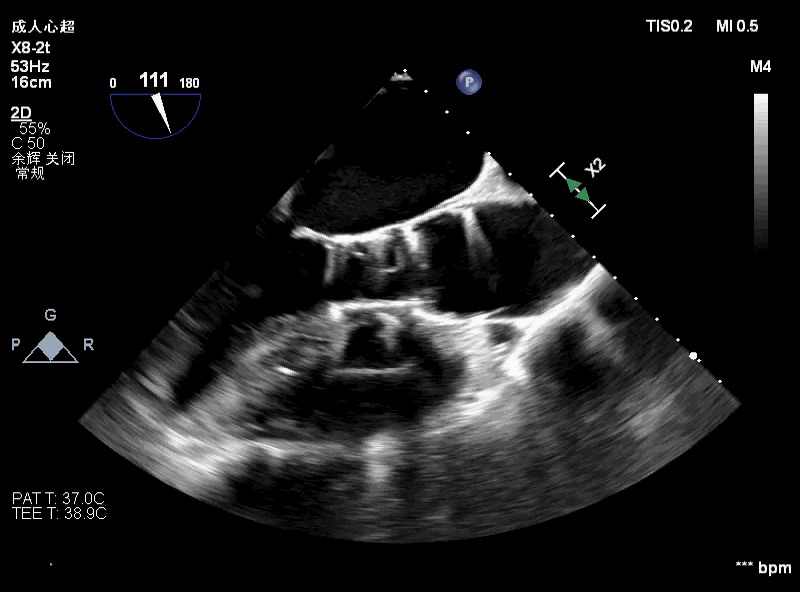

降低原因 — 二尖瓣?

● 考虑超硬导丝缠绕腱索导致二尖瓣关闭受限,予以超声检查。

术前评估主动脉瓣可见中大量反流,二尖瓣轻微反流。

术中超声可见超硬导丝缠绕,二尖瓣大量反流,引起血压无法回升。

撤出输送器,重新调整超硬导丝大小及位置,血压回升,患者情况稳定。